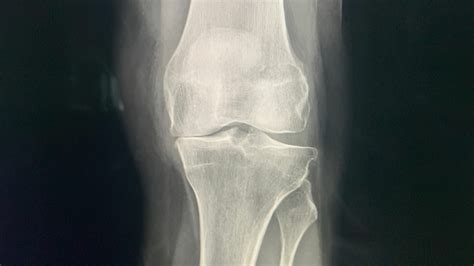

Misschien heb jij wel pijn in je knieën maar twijfel je of dit misschien wel artrose is. De uiteindelijke conclusie zal een arts moeten vaststellen middels lichamelijk onderzoek en eventuele aanvullende onderzoeken zoals een röntgen foto waarop de eventuele artrose zichtbaar zal zijn en ook waar en in welke mate zich deze bevindt in de knie.

Bij de diagnose van knieartrose bepaalt een orthopedisch chirurg het stadium van de slijtage. De conditie van je kraakbeen beoordeelt hij op basis van de classificatie van Kellgren–Lawrence classificatie. Hier lees je hoe deze classificatie eruit ziet en hoe artrose vastgesteld wordt.

Het kraakbeenoppervlak is zachter geworden, waardoor het kraakbeen minder veerkrachtig is. In dit stadium merk je dat je knie minder in staat is om krachten op te vangen. Wanneer er verder onderzoek wordt gedaan met behulp van een röntgenfoto laat deze geen afwijkingen zien. Bij een kijkoperatie lijkt het kraakbeen een blaar te vormen in je knie. Op dit moment heb je nog geen pijn van de slijtage in je knie.

Er is sprake van licht beschadigd kraakbeen: er bevinden zich scheurtjes en onregelmatigheden in het oppervlak, maar deze komen niet verder dan de helft van de oorspronkelijke dikte van het kraakbeen (4 mm). Ook hier toont de röntgenfoto nog geen afwijkingen van betekenis. Je hebt hier al wat pijn van de slijtage in je knie, maar dit is afhankelijk van de mate van belasting.

De scheurtjes vertonen diepere groeven en vormen losse kraakbeenschollen en komen nu verder dan de helft van de oorspronkelijke dikte van het kraakbeen. Dit stadium wordt ook wel pre-artrose genoemd. De gewrichtsspleet begint te versmallen en het bot kleurt witter op de röntgenfoto als teken van verhoogde druk er kan zich ook vocht ophopen in het bot (botoedeem). Er kunnen ruwe uitsteeksels ontstaan. Het kraakbeen verdwijnt. De normale rondingen worden hoekiger, ook wel osteofyten of botapposities genaamd. Dit is het stadium dat voorafgaat aan de versmalling van je gewrichtspleet op een röntgenfoto. Soms brokkelt het kraakbeen aan de randen van het defect af. Deze instabiele kraakbeenranden veroorzaken vaak klachten, zoals kraken, pijn, zwelling en slot- en doorzakklachten. Dit kan plotseling optreden. De pijn van de slijtage in dit stadium is chronisch geworden. In dit stadium kan soms nog wel goed hard gelopen worden.

Het kraakbeen verdwijnt helemaal en het onderliggende bot ligt bloot. Hierbij is vaak de pijn constant aanwezig. De gewrichtsspleet is verder versmald op de röntgenfoto en soms zelfs helemaal verdwenen. Op de foto zijn de kale botvlakken goed herkenbaar.  Er is vaak sprake van zwelling. De zwelling maken bewegen moeilijk. De pijn van de slijtage straalt uit tot in het gebied onder het bot en je gewrichten zijn aan het verstijven en je kan voelen dat de botten over elkaar heen bewegen. In dit stadium is hardlopen niet meer aan te raden.